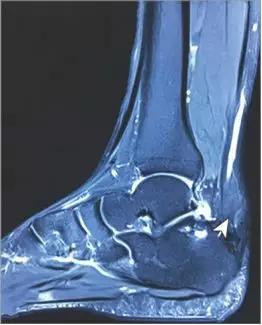

影像学检查发现,脚踝关节MRI提示右侧跟腱处出现梭形增大: